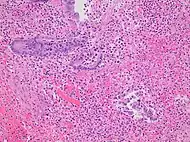

Pathology diagnosis of appendicitis can be made by detecting a neutrophilic infiltrate of the muscularis propria.

Micrograph of appendicitis and periappendicitis. H&E stain

Micrograph of appendicitis showing neutrophils in the muscularis propria. H&E stain

Acute suppurative appendicitis with perforation (at right). H&E stain